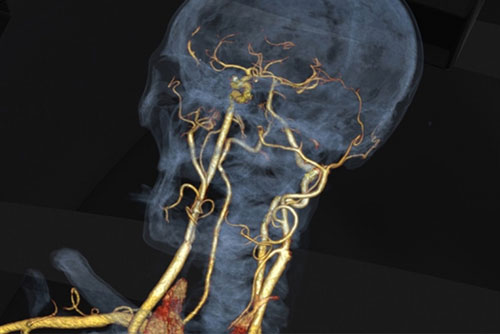

Digital Subtraction Angiography (DSA)

Cerebral Angiogram

Carotid Stenting

Intracranial Stenting